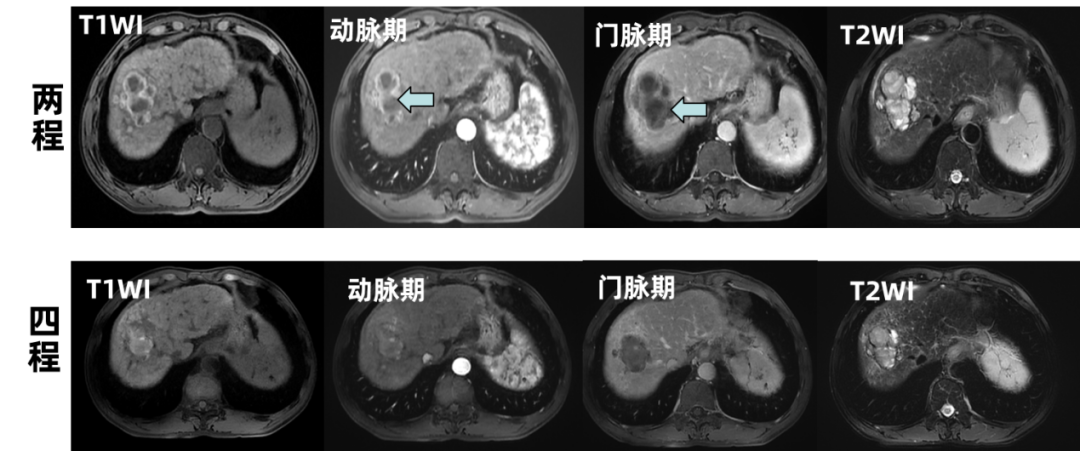

2025-04-11,MR:肝右叶多发肿块、结节,较前稍缩小,强化减低。疗效评价PR。

图6 治疗期间MR检查

本例肝癌(BCLC C期,CNLC IIIa 期)患者,入组了“肝动脉灌注或静脉输注阿得贝利单抗,联合静脉输注贝伐珠单抗及肝动脉灌注-FOLFOX化疗用于晚期不可切除肝细胞癌(HCC)的一线治疗:一项多中心、开放、随机II期临床试验(HAIbrave-001)”,2025-01-03至2025-02-14行两周期肝动脉造影+肝动脉置管术,术后动脉给予FOLFOX+阿得贝利单抗,静脉给予贝伐珠单抗,肿瘤标志物逐步下降,疗效评价PR;2025-03-07至2025-03-28行第3-4周期肝动脉置管术,术后动脉给予FOLFOX+阿得贝利单抗,静脉给予贝伐珠单抗,治疗四周期复查病灶较前缩小,疗效评价PR,肿瘤标志物恢复接近正常。